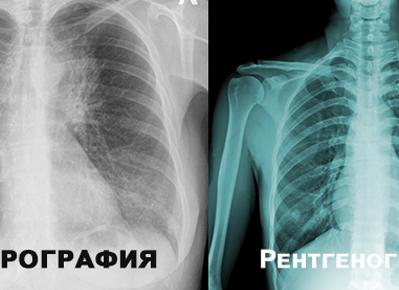

В поликлиниках с профилактической целью выполняется флюорография. Чем отличается от рентгена проведение этого обследования? При прямом прохождении лучей на экране отображается структура органа, а при флюорографии снимается его тень, отраженная от флюоресцирующего экрана. Аппараты для этих видов исследований различаются по конструкции.

Рентгенография грудной клетки – неинвазивный метод обследования тканей и органов с помощью одноименных лучей. Результат выводится на пленочный снимок. Это обследование тоже является радиологическим. Чем отличается флюорография от рентгена грудной клетки для простого обывателя, так это размерами готового результата — вместо маленького неразборчивого квадратика выдается проявленная пленка 35 х 35 см.

При рентгенографии R-лучи проходят сквозь тело человека и попадают сразу на пленку, а при флюорографии прежде совершается преобразование этих лучей в видимый свет с дальнейшей фокусировкой изображения, которое отправляется на фотопленку в уменьшенном виде.